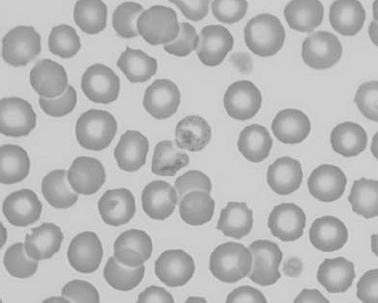

See Figs 1.3–1.24 for pictures of various types of RBC morphology.

Figure 1.19 Canine blood film showing microcytic, hypochromic erythrocytes consistent with iron deficiency anemia. There are two polychromatophils in the field, indicating that the anemia is regenerative (also see color section).

Red cell breakdown products are not available for recycling when blood is lost from the body. Chronic or recurrent external blood loss can be caused by disorders of primary hemostasis, such as thrombocytopenia and von Willebrand disease; infestation with internal or external bloodsucking parasites; intestinal hemorrhage from ulcers (drug or stress induced), enteritis, or neoplasms; and genitourinary bleeding. Bleeding into the intestinal and genitourinary tracts is truly external blood loss because RBCs are not available for recycling. Iron is lost from the body and, given sufficient time, erythropoiesis is affected. Iron deficiency anemia is a continuum and, if uncorrected, microcytosis and hypochromia eventually develop. Hemoglobinization of rubricytes and metarubricytes is impaired and the delay in incorporation of iron results in an additional mitotic division in erythroid cells. This additional mitosis is responsible for microcytosis in developing erythrocytes. The lack of iron causes hypochromia in advanced cases, which is identified as pale cells with increased central pallor; fragility and fragmentation of erythrocytes due to the paucity of intracellular hemoglobin; and decreases in MCH and MCHC. Despite the lack of iron, the anemia is often regenerative at the time of initial detection. The regenerative response may not be as robust as with anemias that are not associated with iron lack, such as hemolysis or internal hemorrhage. Tests that help to confirm iron deficiency are serum iron; total ironbinding capacity (TIBC), which is a measure of transferrin, the iron-binding protein; serum ferritin; and visual evaluation of marrow iron stores. Serum ferritin and bone marrow examination are the best ways to assess total iron stores in the body. Serum iron is affected by many conditions besides iron status. However, low serum iron and high TIBC are expected in iron deficiency in most species, except the dog. In this species, the TIBC is not necessarily increased with iron deficiency. Although serum iron is also decreased with anemia related to chronic inflammation, the TIBC is low to normal with this condition. Serum ferritin assays are not readily available for all species, and bone marrow examination is an invasive procedure if iron status is the only concern. Often the history, clinical findings, and peripheral blood findings are sufficient to diagnose iron deficiency anemia. The etiology of the iron lack must then be determined.